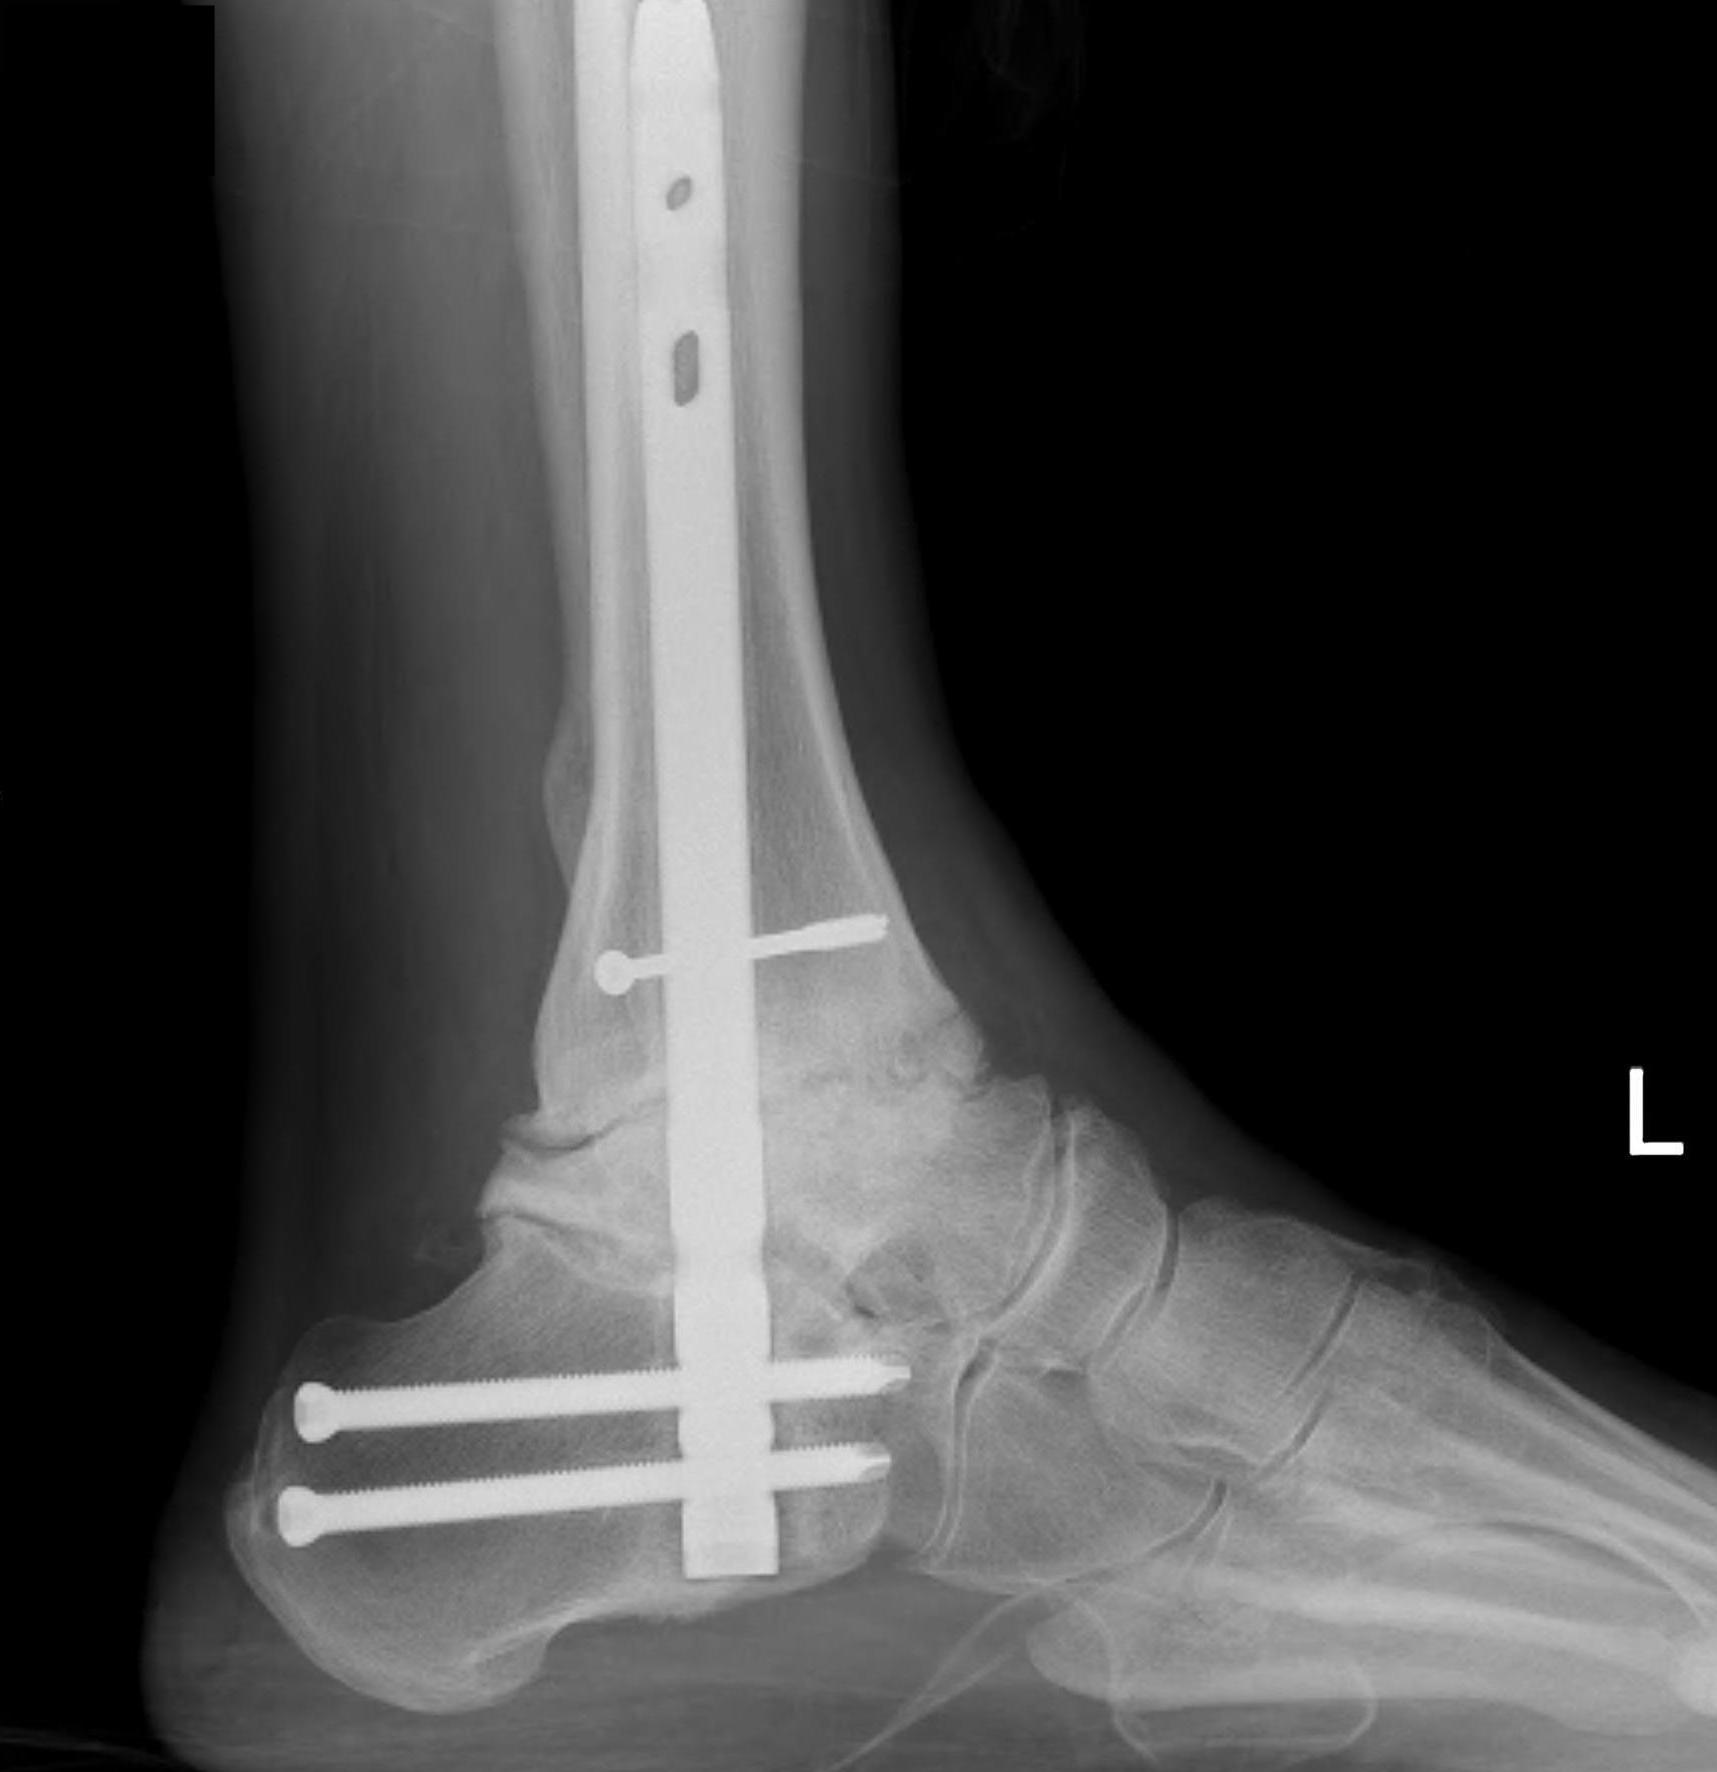

Tibiotalocalcaneal (TTC) / hindfoot nail

Insertion point

- in line with 2nd metatarsal / center of heel pad

- junction of posterior 2/3 and anterior 1/3 heel

- should pass through anterior aspect posterior subtalar joint

- posterior to lateral plantar artery and nerve

Screw fixation

- distal screw fixation in calcaneum +/- talus with jig

- compression

- proximal screws medial to lateral